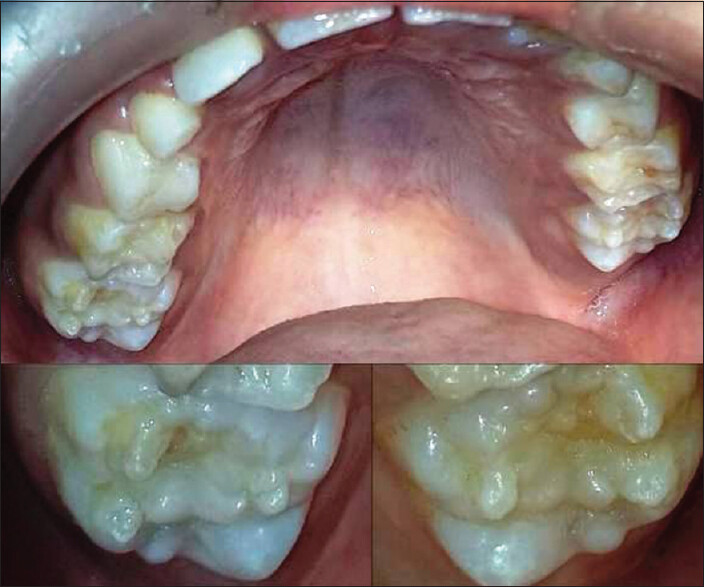

Mulberries. They sound like something you find in a scrumptious pie or jam. Mulberry molars, on the other hand, are a tough pill to swallow. After your child loses their baby teeth, their permanent teeth come in when they're around 5 or 6. Occasionally these fresh molars are abnormally shaped with small bumps, reminiscent of mulberry fruits, according to the Rutgers School of Dental Medicine. While mulberry molars can be alarming for parents — they can be easily treated.

Often, dentists in developed countries have never treated a case of mulberry molars, notes the Head and Neck Pathology report. But they should be able to identify it as the bumpy surface makes the condition very recognizable. Syphilis is diagnosed via a blood test. Antibodies to the bacteria are present in the blood of those with syphilis. It's a severe condition if passed along to babies — consequently, pregnant women should be tested.

Cavities commonly occur if mulberry molars are present. For that reason, crown restorations help not only the look of the teeth but also their strength. Your pediatrician should be able to treat syphilis in children with mulberry teeth by administering penicillin. If allergic to penicillin, antibiotics may also be a course of action.